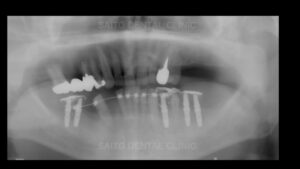

お口の中を見せていただくと左上の奥歯と右下の奥歯が失われています

そして前歯がうまく噛み合っていないので実質噛める歯がほとんどなく

奥歯が壊れるに従って噛み合わせの高さも失われて下の前歯が上の顎に刺さってしまうような状態です

そして奥歯にインプラント治療をしていきますが右下の部分は顎の骨の中の神経付近まで

歯周病によって顎の骨が溶けてしまっているためインプラントができません

また、骨を作る手術も神経が近いため麻痺の可能性を考えるとそれもできません

そこで右下は手前の歯をインプラントで引っ張って周囲の骨ごと引っ張ってその手前に

インプラントを植える治療方法としました